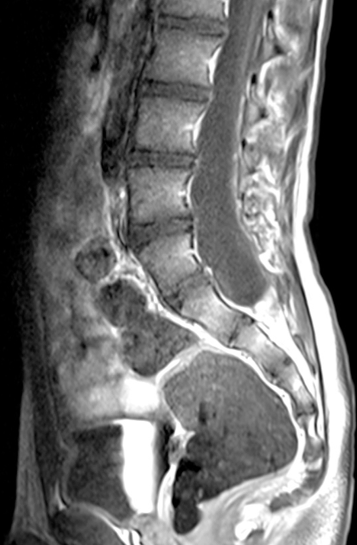

le lipome

à distinguer des lipomes dysraphiques, il s’agit ici d’une inclusion intra-névraxique, évolutive avec la masse graisseuse de l’enfant, qui peut se révéler dans les premiers

mois de vie.

la chirurgie a un but de décompression, elle est limitée par l’absence de plan de clivage ; ici aussi, c’est une intervention de plastie ostéo-durale, mais dont l’efficacité peut être très salutaire et durable

en raison du jeune âge de l’enfant et de la localisation souvent haute, la prise en charge orthopédique (minerve) et la rééducation sont d’importance capitale.